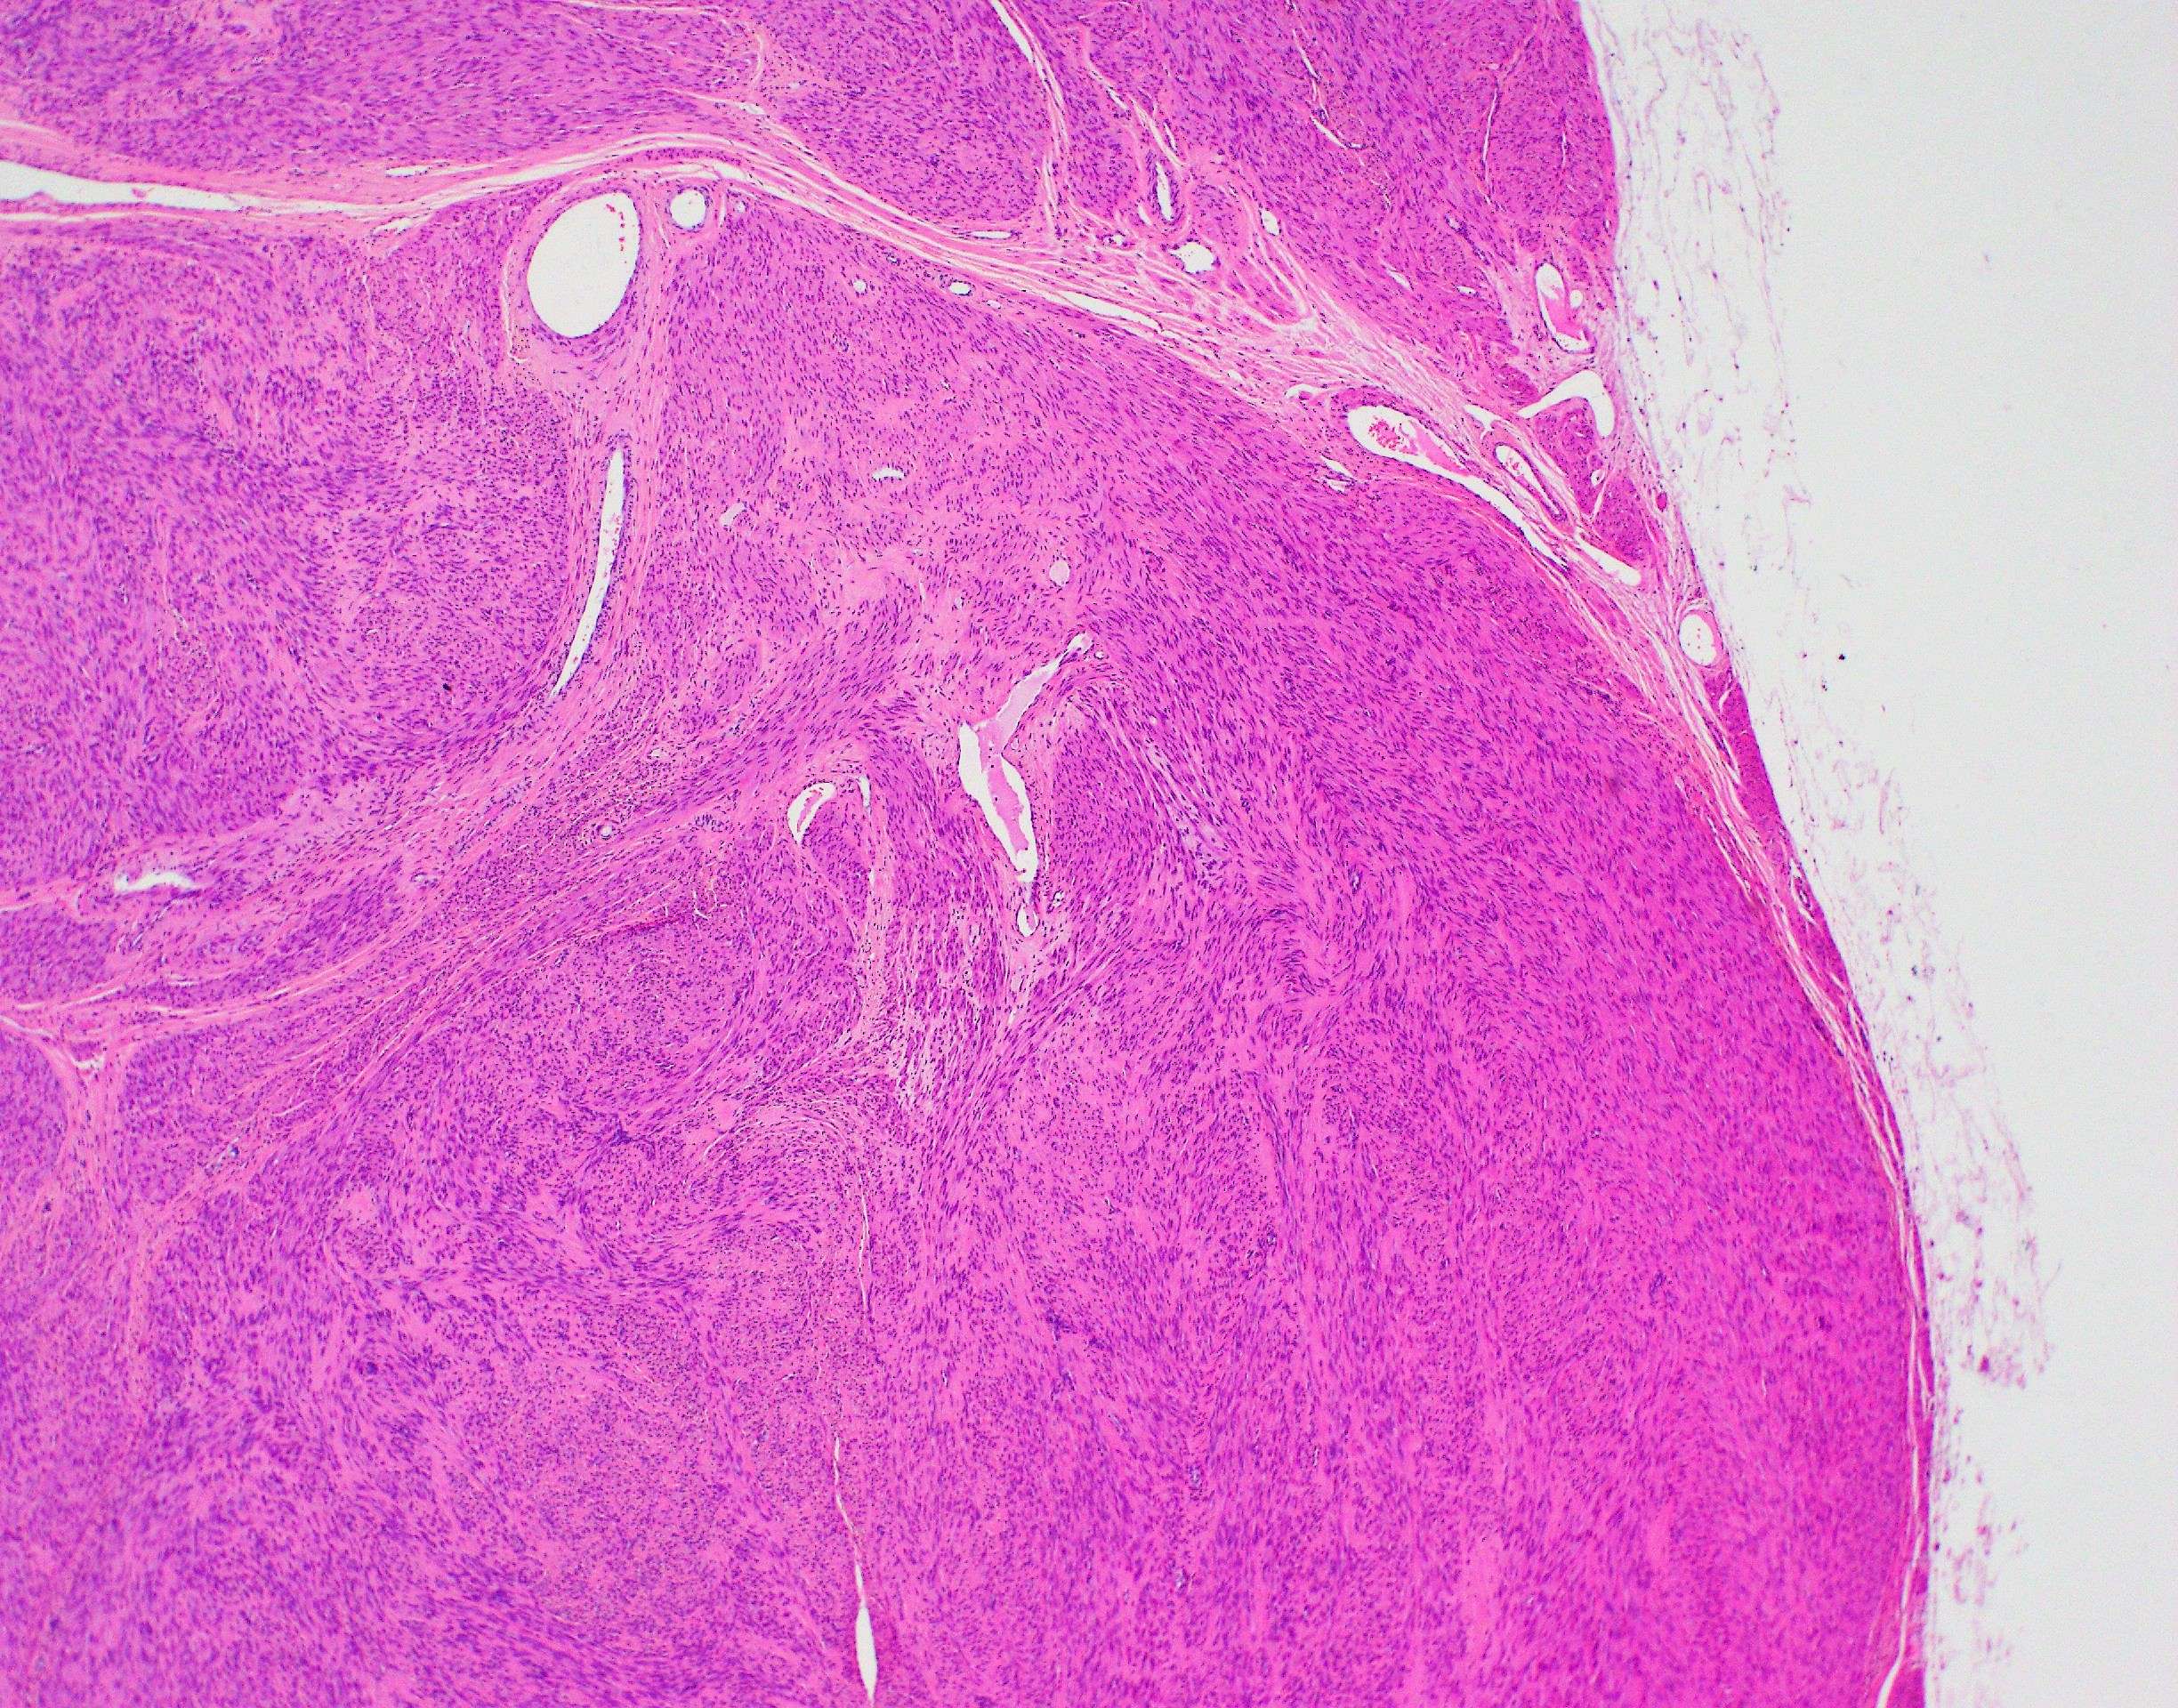

Leiomyoma Of The Uterus | Ottawa Atlas Of Pathology

www.pathologyatlas.ca

www.pathologyatlas.ca

Leiomyoma Of The Uterus | Ottawa Atlas Of Pathology

www.pathologyatlas.ca

www.pathologyatlas.ca